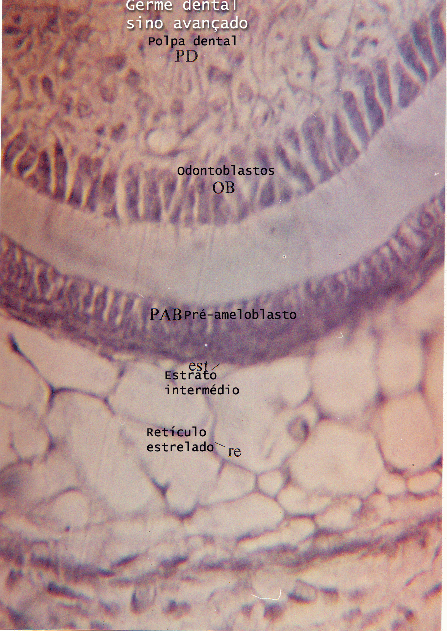

Desenvolvimento da face e odontogênese - Face and Tooth formation